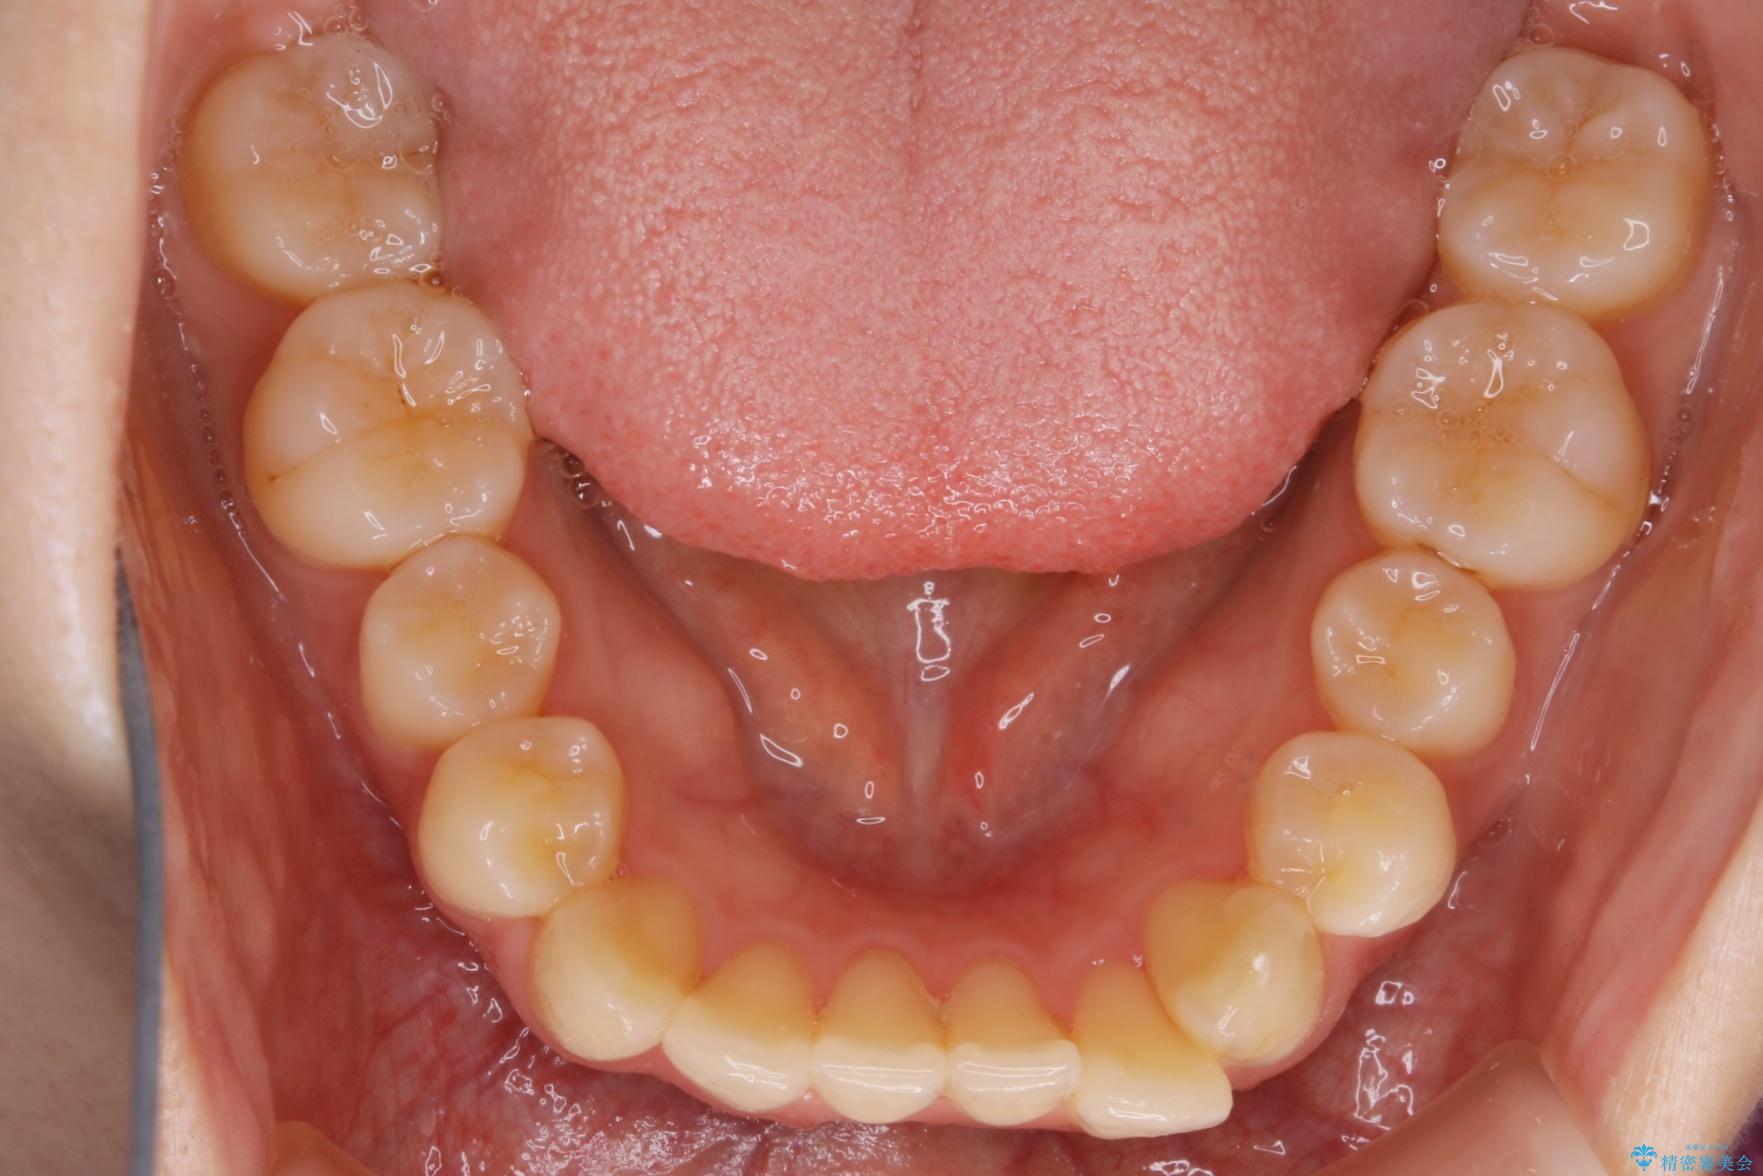

下の前歯のガタつきが気になるとご来院された患者様です。

インビザラインのライトパッケージにて、歯列拡大とディスキング(IPR)をを行いスペースをつくり非抜歯で治療を行いました。

ディスキング(IPR)

歯のガタつきをとるためのスペース作りの方法の一つにディスキング(IPR)という方法があります。

歯と歯の間を一ケ所あたり最大0.5mmまでの範囲内で削ることで歯自体が少し小さくなり、それにより作られるスペースを数ヶ所分合わせることで合計で数mmの大きなスペースが作れるという方法です。

当院ではなるべく歯の機能や見た目に影響の出ないよう、作業時に拡大鏡の使用や削るタイミングの微調整を行っています。